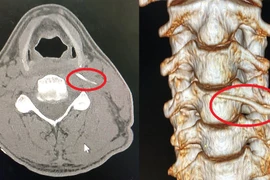

Nam thanh niên 17 tuổi (ở Kiên Giang), thường xuyên bị sốt, ăn uống khó khăn, có khối sưng to ở cổ, sợ bị ung thư nên đi khám. Tuy nhiên, kết quả xác định nam thanh niên bị hóc xương cá "di cư" ra vùng cổ.

Với những dị vật cắm sâu, các bác sĩ phải giải phóng trước phần đầu xương “ăn” sâu vào thành họng, sau đó mới rút theo hướng trước – sau để hạn chế tổn thương.